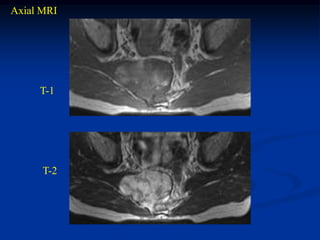

Case #1101

Axial T-1 MRI

60 year female with chordoma sacrum

Axial T-2 MRI

Sagittal T-2 MRI